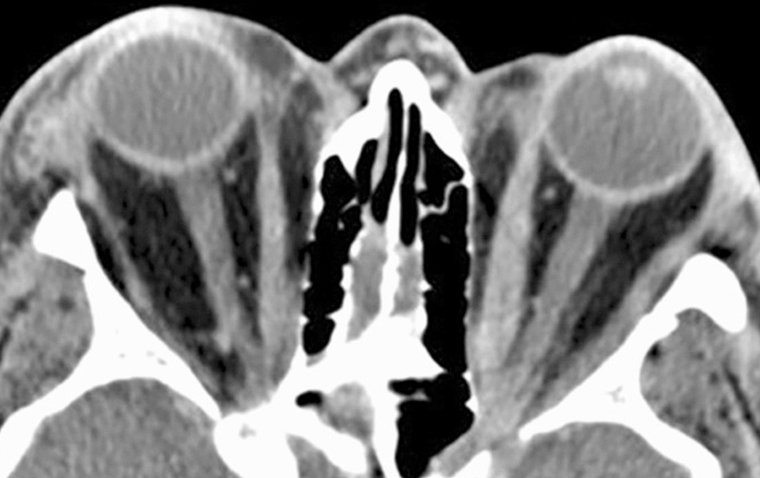

Timely and accurate diagnosis is critical in managing DON effectively. Ophthalmologists employ various techniques, including visual acuity tests, assessment of eye movements, and imaging modalities like computed tomography (CT) and magnetic resonance imaging (MRI). These tests help evaluate the extent of orbital involvement and optic nerve compression, aiding in appropriate treatment planning.

Orbital decompression surgery is considered for patients with severe DON, particularly those experiencing optic nerve compression and significant proptosis. This surgical procedure involves removing or reshaping portions of the orbital bones to create more space within the orbit. By doing so, pressure on the optic nerve is reduced, potentially preventing vision loss and improving the appearance of bulging eyes.